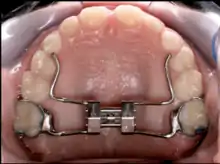

Palatal expansion

Palatal expansion can be best achieved using a fixed tissue-borne appliance. Removable appliances can push teeth outward but are less effective at maxillary sutural expansion. The effects of a removable expander may look the same as they push teeth outward, but they should not be confused with actually expanding the palate. Proper palate expansion can create more space for teeth as well as improve both oral and nasal airflow.